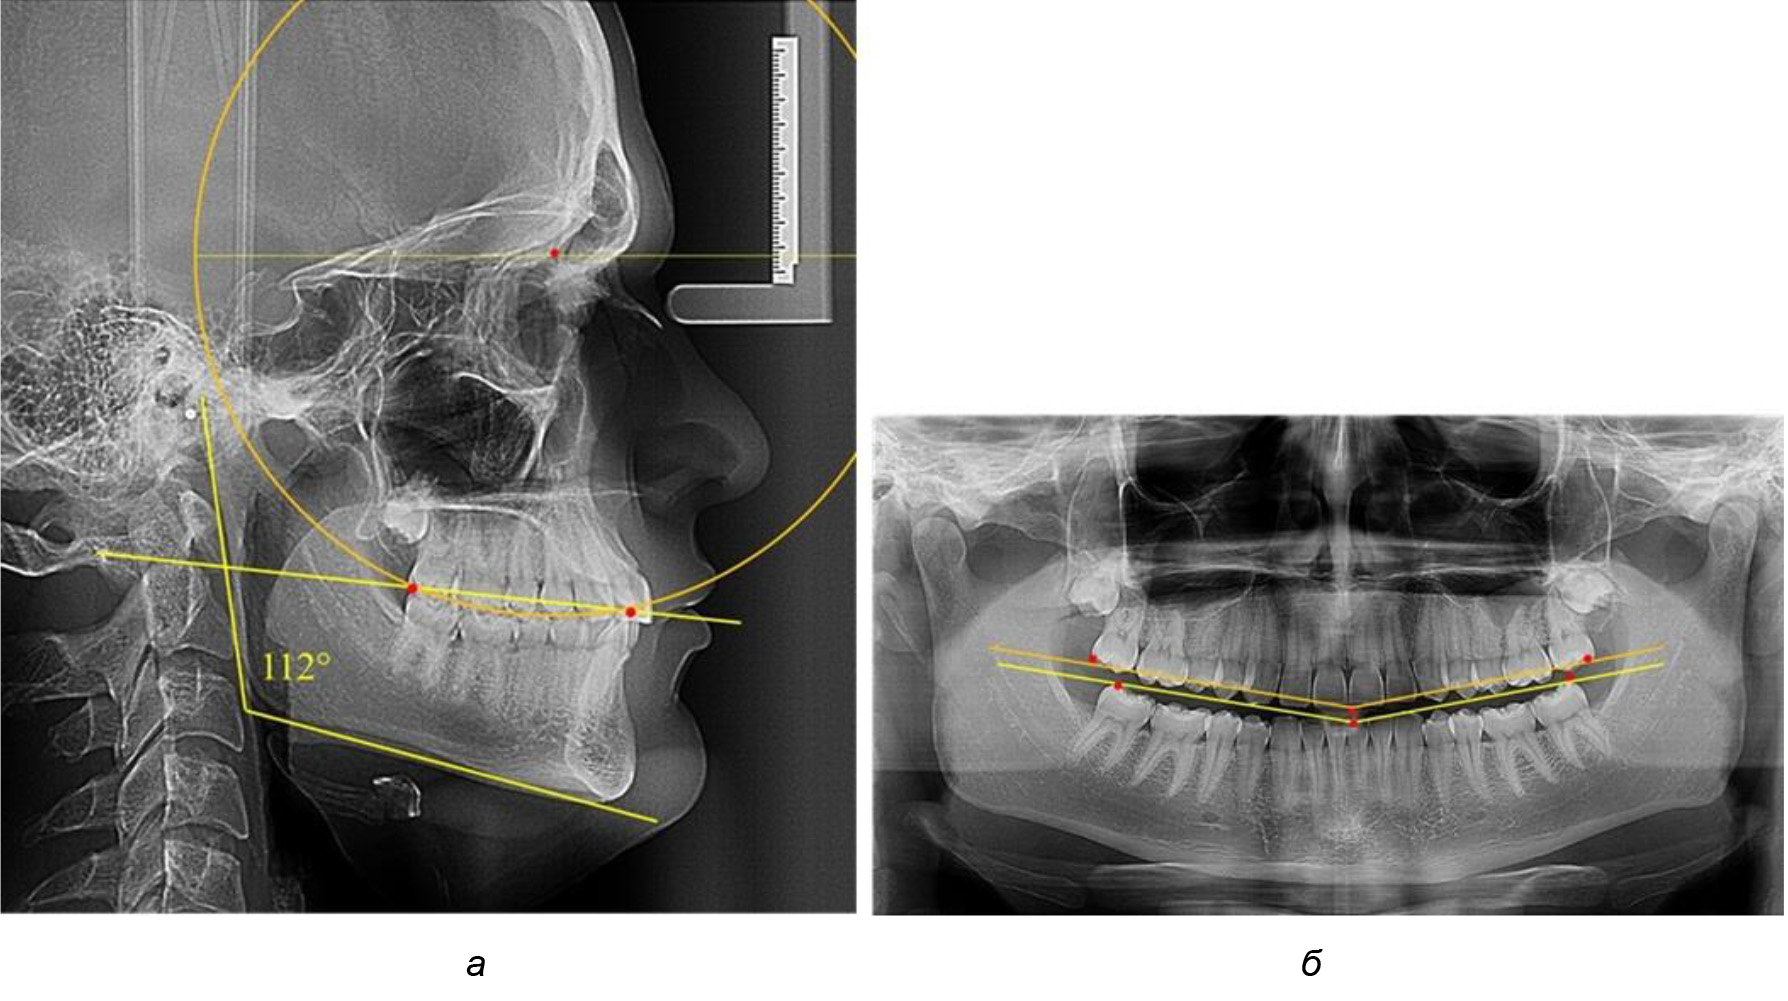

Во 2-й подгруппе 2-й группы было обследовано 7 человек.

Указанная величина не имела достоверного отличия с 1-й подгруппой (р ˃ 0,05), что определяло однородность групп по количественному признаку.

Обращает на себя внимание, что глубина кривой Spee в анализируемой подгруппе практически не отличалась от показателей, полученных у людей с физиологической окклюзией, и составляла (4,23 ± 1,58) мм. Отношение радиуса окружности к сагиттальному размеру окклюзионной линии в среднем по подгруппе составляло 1,623 ± 0,02 и соответствовало числу Фибоначчи.

После лечения пациентов техникой «прямой» дуги, так же как и в 1-й подгруппе, было отмечено увеличение сагиттального размера окклюзионной лини в среднем на (2,38 ± 0,83) мм. Окклюзионная линия практически касалась окклюзионного контура всех жевательных зубов, и отмечалось практически полное отсутствие кривой Spee, так же как и у людей 1-й подгруппы 2-й группы (рис. 6).

Рис. 6. Особенности ТРГ при оптимальной кривой Spee до лечения (а) и после лечения (б) техникой «прямой» дуги

Таким образом, проведенное лечение техникой «прямой» дуги способствует нормализации окклюзионного равновесия и торку передних зубов, однако не соответствует оптимальному окклюзионному статусу, характеризующему физиологическую окклюзию. При этом величина нижнечелюстного угла оставалась на прежнем уровне.